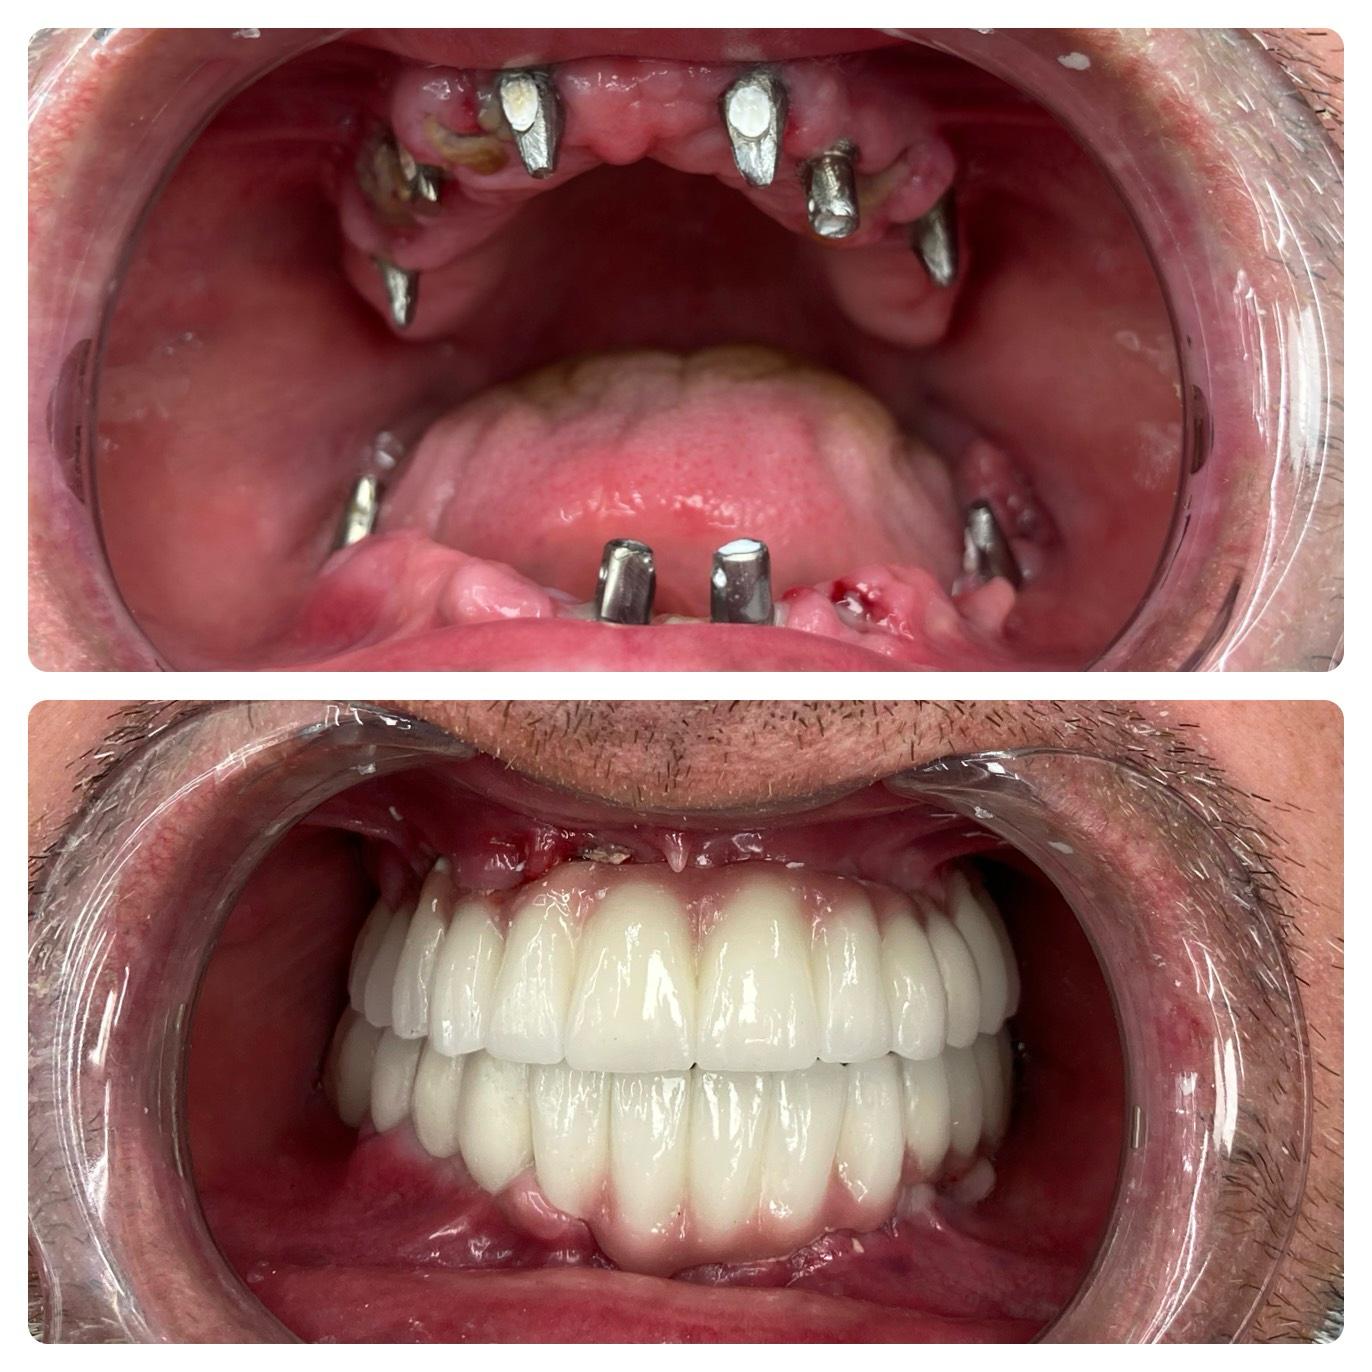

Si inizia con una consulenza e immagini 3D. Gli impianti vengono posizionati con precisione e restaurati con corone che appaiono e funzionano come denti naturali. L’intero processo è attentamente pianificato in fasi: valutazione, posizionamento dell’impianto, periodo di guarigione e restauro finale. Con le tecniche moderne, molte procedure sono minimamente invasive e spesso vengono fornite soluzioni temporanee, così da non rimanere mai senza sorriso durante il trattamento.

Gli impianti dentali rappresentano lo standard d’eccellenza per sostituire i denti mancanti, offrendo stabilità, durata e un aspetto e una sensazione naturali. Non migliorano solo l’estetica — ripristinano anche la capacità di masticare, preservano la struttura del viso e aiutano a prevenire la perdita ossea della mandibola. Per molti pazienti, gli impianti non sono solo cosmetici, ma essenziali per la salute orale a lungo termine e la fiducia complessiva.